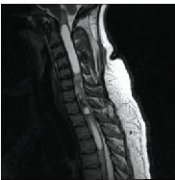

脊髓肿瘤 约占中枢神经系统肿瘤的15%,大多数硬膜内肿瘤起源于脊髓和终丝、神经根或脑膜的细胞成分。脊柱硬膜内腔的转移很少表现为肿块病变。硬膜内脊髓肿瘤是根据其与脊髓的关...

脊髓肿瘤 ,也称椎管内肿瘤(intraspinal tumors),是发生于脊髓本身及椎管内与脊髓邻近组织(脊神经根、硬脊膜、脂肪组织、血管、先天性残留组织等)的原发性肿瘤或转移性肿瘤的总...